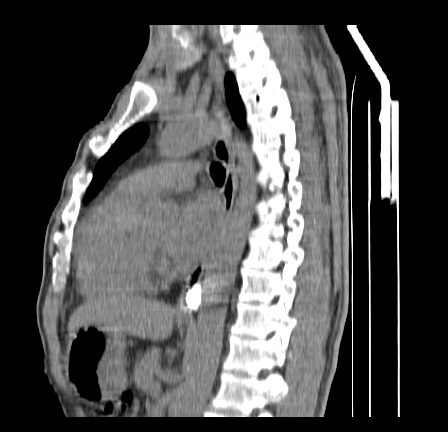

以下是引用影像孺子牛在2009-5-20 23:18:00的发言:[br]左侧后心膈角处类椭圆形钙化灶,最常见的是淋巴结钙化,但太大了不支持,其它如食管囊肿钙化、实性畸胆瘤等。何东西钙化真不好定。